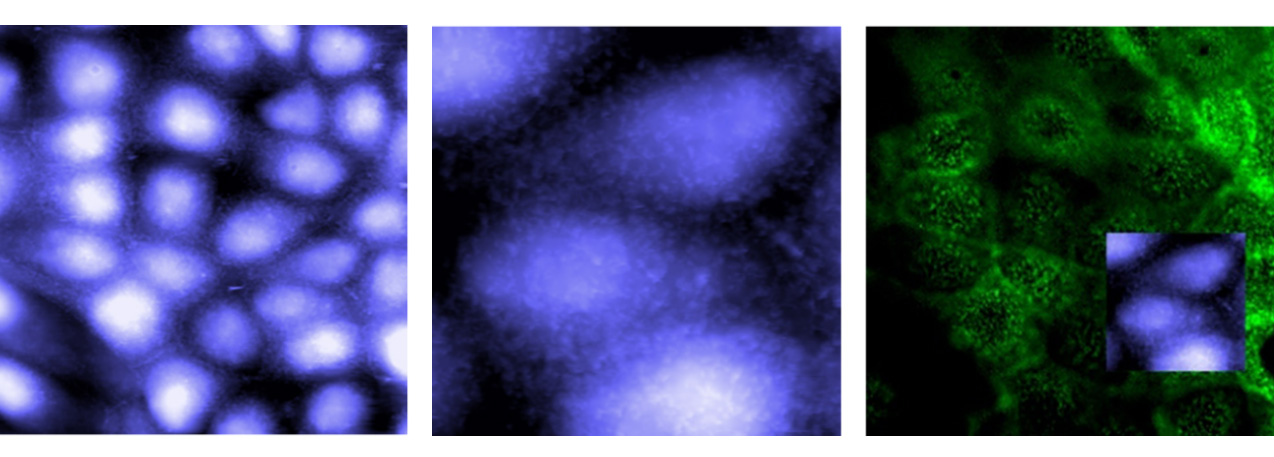

Dynamic morphological changes in living HUVEC cell, imaged at 37°C in full growth medium. Consecutive phase channel images show dynamic cellular events such as cytoskeleton reorganization (circle). Scan size: 7.17x7.17 µm. Sample courtesy of Prof. Dr. Stefan Zahler, LMU München, Germany.